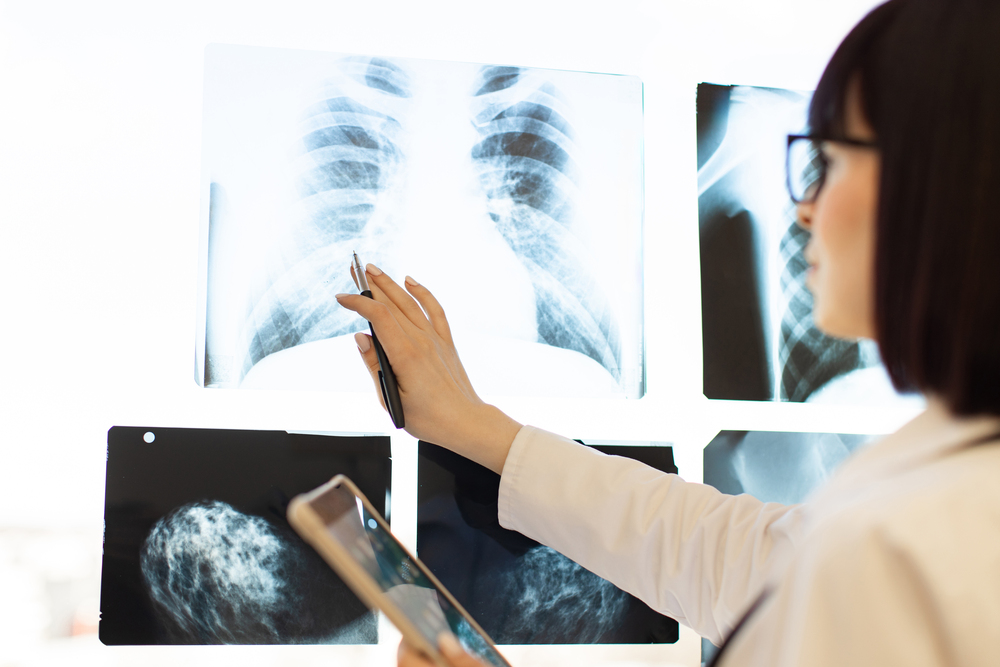

La radiografía de tórax utiliza radiación ionizante en dosis mínimas para crear imágenes detalladas de los órganos internos. Los especialistas la emplean para diagnosticar diversas condiciones respiratorias y cardíacas, ofreciendo una herramienta fundamental en el diagnóstico médico.

Instrucciones del Personal Médico

El tecnólogo radiológico proporcionará indicaciones precisas sobre:

- Momentos para respirar

- Técnicas de inmovilización

- Coordinación durante la exposición

Resultados

- Disponibilidad: 24-48 horas

- Interpretación por radiólogos

- Informes detallados al médico tratante